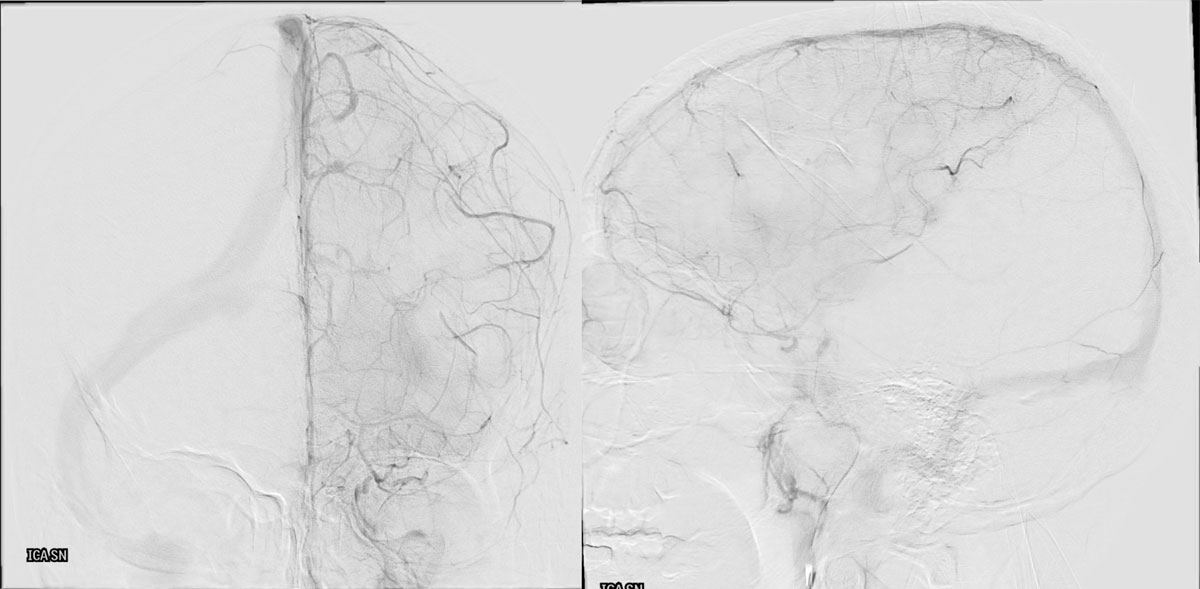

DSA

L - ICA